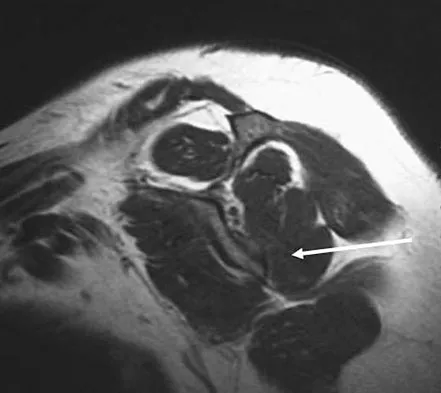

Figure 50 shows the cross table lateral radiograph of a 31-year-old paratrooper who has recalcitrant groin pain. The pain is worse after activities such as standing or sitting (driving). Examination reveals that pain can be reproduced by internal rotation of the leg with the hip and knee in 90 degrees of flexion. Extensive nonsurgical managment has failed to provide relief. What is the treatment of choice?